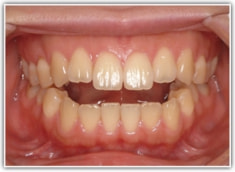

治療前

かなり重度のオープンバイト症例です。骨格的な要素も強く出ております。通常であれば外科矯正適応のパターンですが、当院では矯正治療のみで、外科は行いません。